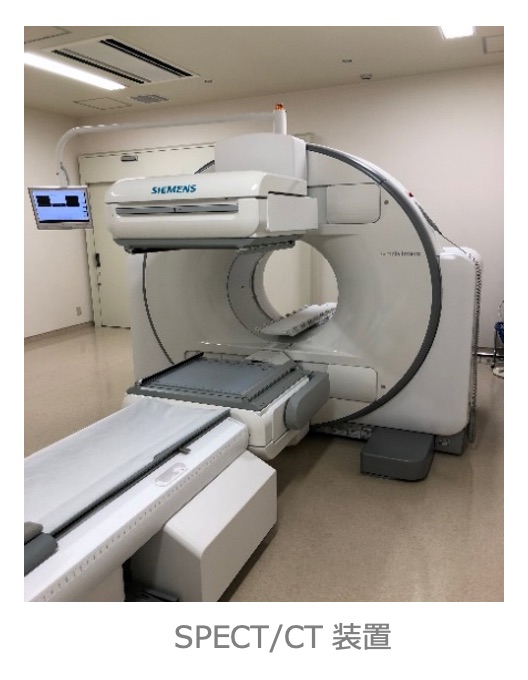

| 核医学検査 | 5室 | PET/CT×3台 SPECT/CT×2台 |

核医学検査(RI 検査)

放射性同位元素(Radio Isotope:RI )を用いた検査のことで、目的とする臓器や腫瘍に集まる薬にRIで目印を付けて投与し、放出される放射線(ガンマ線)を専用のカメラで計測します。 核医学検査はSPECT(スペクト)とPET(ペット)に分けられ、さらに心臓、脳、肺、骨、腫瘍など検査目的によって多くの検査に分けられます。

当院の核医学検査(PET検査、SPECT検査)は核医学専門技師の認定を受けた診療放射線技師を中心とし、放射性医薬品の管理や機器精度管理のもと撮影を担当しています。

●SPECT検査︓ Single photon emission computed tomography